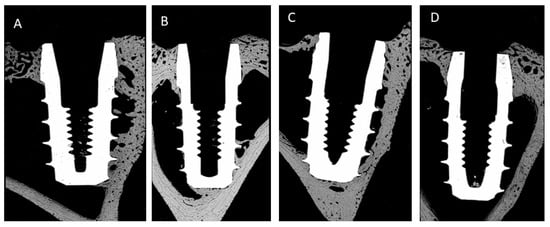

- Case A: 0.5 mm above the bone surface (h = +0.5).

- Case B: at the same level of the bone surface (h = 0).

- Case C: 0.5 mm below the bone surface (h = −0.5).